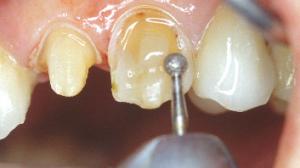

Des tranchées verticales sont réalisées avec la même fraise boule et à la même profondeur que le premier sillon (0,5mm).

Une ou plusieurs tranchées horizontales réunissent les tranchées verticales.

Une fraise à congé termine la préparation vestibulaire.

La préparation de la face vestibulaire est terminée. La limite est pour le moment supra gingivale.